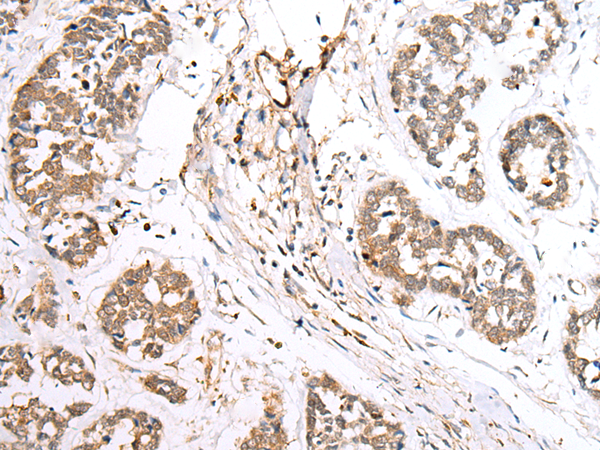

The image is immunohistochemistry of paraffin-embedded Human esophagus cancer tissue using P12542(BAG2 Antibody) at dilution 1/40. (Original magnification: ×200) |